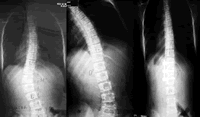

青少年特发性脊柱侧凸(AIS)是10岁以上儿童在发育成熟前常见的一种非先天性脊柱畸形,2%~3%的青少年有此畸形,其占全部脊柱侧凸病例的80%。由于脊柱侧凸、扭曲和胸廓变形会直接影响患者的外观、心肺功能和生活质量,并严重危害他们的身心健康,因此,应重视AIS的早期诊断和治疗,尽早矫正畸形。

AIS的治疗方案包括非手术治疗和手术治疗,一般将侧凸的冠状面Cobb角是否超过40°作为是否选择手术治疗的决策依据。

临床上通常根据冠状面的Cobb角、骨骼发育情况、脊柱矢状面变化、椎体旋转程度及侧凸的自然病史判断是否需手术治疗。一般认为,对处于生长期、Cobb角>40°、非手术治疗无效(6个月内侧凸进展超过5°)、伴有疼痛、胸椎前凸及伴明显外观畸形的患者应选择手术治疗 ......